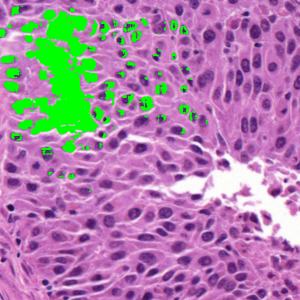

Table 1, on Dataset 2, shows that SP obtained the highest DSC (88.78), which is higher by 5.90, 7.09, 8.31, and 22.46 compared to SAM, ZZ, SMST, and AR, respectively. The segmentation time of SP was 14.55s, approximately twice that of SAM (the second fastest method without considering pre-processing times), and more than one order of magnitude lower than the level-set methods AR and ZZ. While AR and ZZ need user-specific markers as input (the pre-processing time indicated as \infty), SAM needs to load the pre-trained model (6.09s) while SP and SMST need to generate the superpixels in the pre-processing step (0.08s). Figure 11 shows the resulting segmentations for two example images from Figs. LABEL:fig_sub:he3_image and LABEL:fig_sub:he4_image from Dataset 2. The segmentations reflect the trends observed in Table 1, with SP achieving the highest DSC and segmentation times exhibiting a similar relative order.

Refer to caption

Figure 11: Segmentation of two images from the quantitative comparison on Dataset 2 (S3 and S4, Figs. LABEL:fig_sub:he3_image and LABEL:fig_sub:he4_image); brackets show segmentation time (s) / DSC.